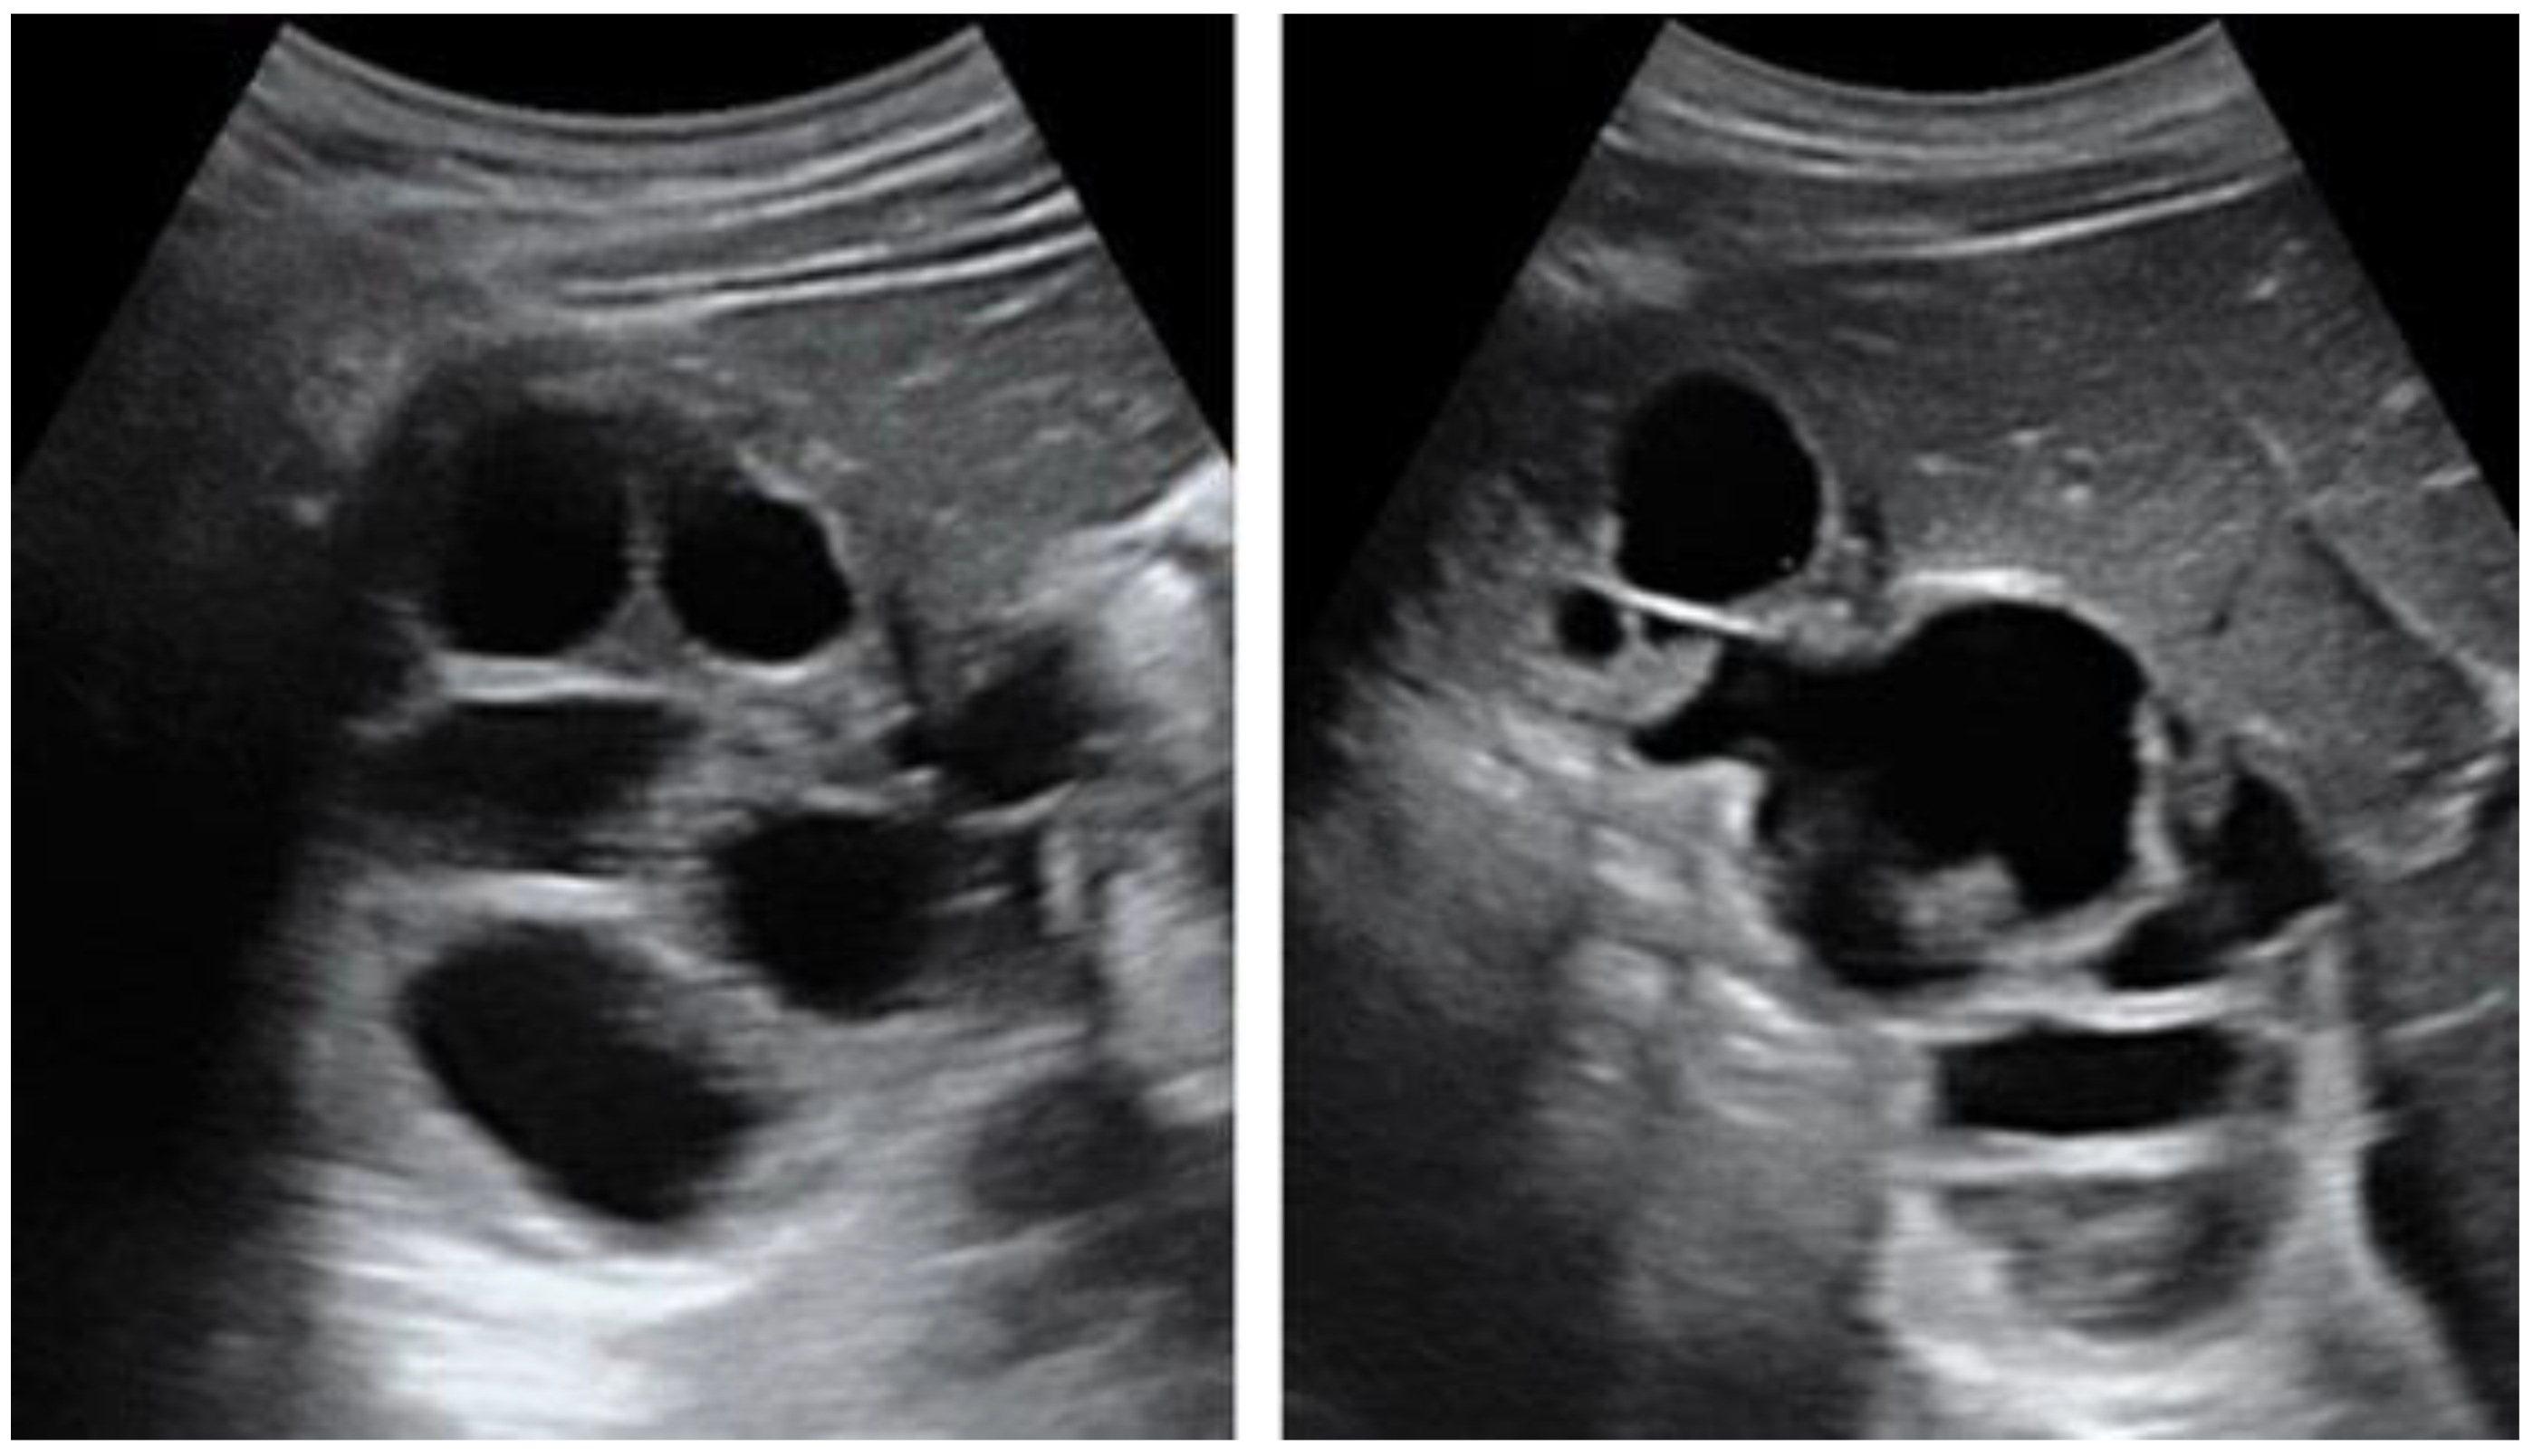

5.1. Hydatid Cysts of the Liver